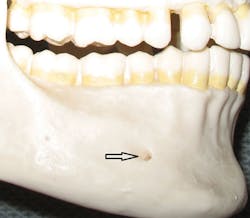

Figure 2: Mental foramen

Since only the soft tissues are anesthetized by the mental block, the incisive block is preferred for nonsurgical periodontal therapy procedures. The mental foramen, which opens anteriorly and superiorly, is usually located near the apex of the second premolar (see Figure 2), although studies indicate that it can be located from the distal of the canine to the first molar.3-5 It is advisable to check the radiographs and palpate the area prior to procedures to determine its location. The foramen appears as a round or oval radiolucency on radiographs (see Figures 3, 4) and may be palpable as a concavity or rough elevation.2